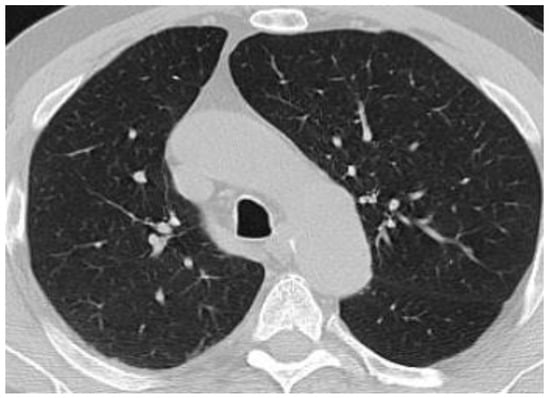

5. ICI Therapy-Related Pneumonitis